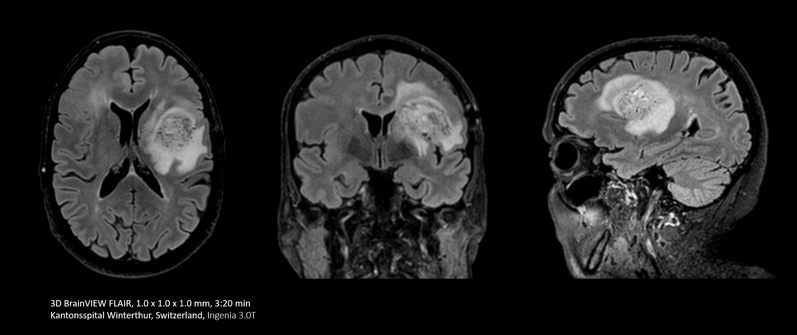

Compressed SENSE permette di sostituire, in soli 3 minuti e mezzo, una scansione FLAIR in 2D a orientamento singolo con una scansione FLAIR volumetrica in 3D a orientamento multiplo.

Personalmente eseguo molti esami di imaging cerebrale. Prima, per la sequenza FLAIR utilizzavamo una sezione di 5 mm di spessore. Ora, grazie a Compressed SENSE, siamo in grado di eseguire una scansione volumetrica in 3D in circa 6 minuti che possono scendere fino a 3 minuti e mezzo."

Dott. Mark Oswood, neuroradiologo presso Hennepin Healthcare, Minneapolis (Stati Uniti)